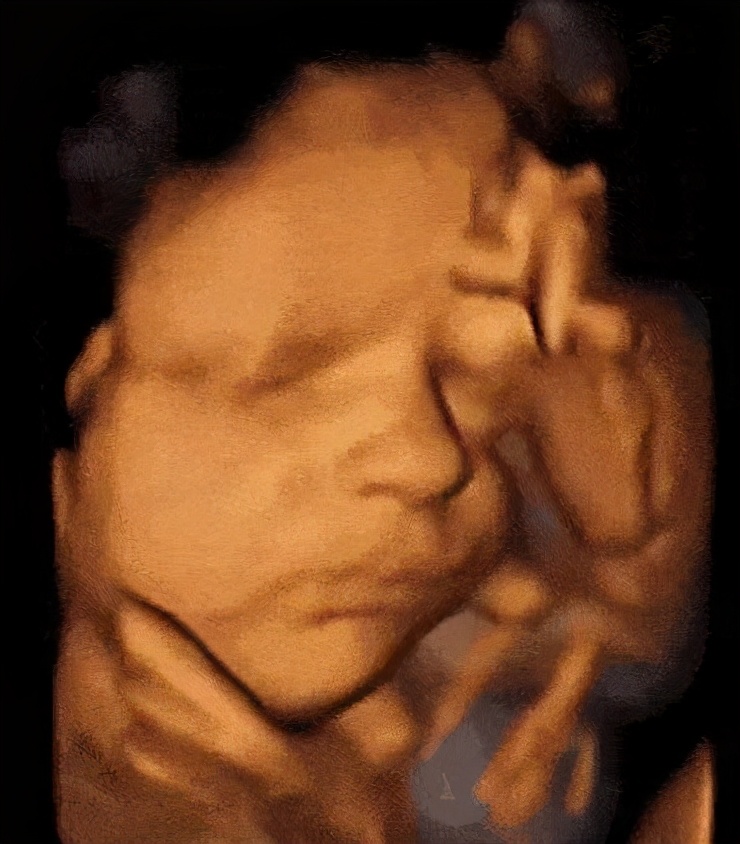

三维图像是这样的

目前产前超声技术包括二维、三维、四维技术,二维是平面成像,三维是立体成像,四维是三维加上时间的维度,即动态的三维,通过表面成像模式、骨骼成像模式、血管成像模式等由计算机进行三维重建,简单来说就是动态的观察宝宝在妈妈肚子里的活动情况。

实际上,彩超并不是维数越高越好,大家关注的三维技术是在二维超声的基础上进行成像,二维是基础,三维、四维是超声技术的辅助。目前大家对三维、四维有一个误区,认为三维、四维看的更清楚,所以经常有孕妈妈要求做三维、四维超声来确诊宝宝畸形,我们一般会告知孕妈妈医生是通过二维图像来观察宝宝是否正常,如果发现宝宝有结构的异常,医生才会使用三维、四维技术扫查,以此确诊,如果孕妈妈们想看到宝宝面部的虚拟照片,选择三维彩超就可以了哟!